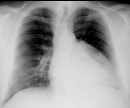

Cough and Dyspnea

Larry Hudgins, MD; Thomas M. Roy, MD; Said B. Iskandar, MD; Muhanad A. Al Hasan, MD; Vipul Brahmbhatt, MD

<div id="article-content-body"> <p><em><img alt="" src="/sites/default/files/images/ConCPEmpy3.jpg" style="border:1px solid black; height:139px;...